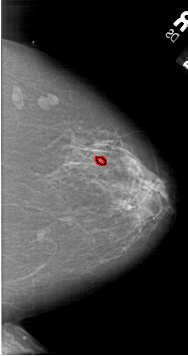

A_1646_1.RIGHT_CC

RIGHT_CC LINES 6391 PIXELS_PER_LINE 3376 BITS_PER_PIXEL 12 RESOLUTION 43.5 OVERLAY

FILE: A_1646_1.RIGHT_CC.OVERLAY

TOTAL_ABNORMALITIES 1

ABNORMALITY 1

LESION_TYPE CALCIFICATION TYPE PLEOMORPHIC DISTRIBUTION CLUSTERED

ASSESSMENT 3

SUBTLETY 2

PATHOLOGY BENIGN